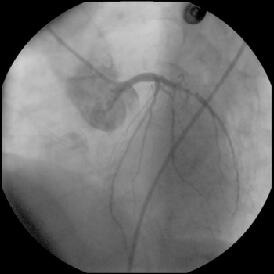

しかし、KBT直前の像(『ChoicePT2.GW.Prolapse』)では屈曲していただけの#9に挿

入したChoice PT2 LSが、KBT時像からは屈曲とともに先端1cm程度が断裂し

(『ChoicePT2.GW.Fracture』)、#9の末梢枝に遺残してしまいました

(『ChoicePT2.Fnl』2枚)。幸い虚血所見がまったくありませんでしたので手技は終

了とし、術後のCK逸脱もなし、翌日お元気に退院されました。

ステント留置の際にChoice PT2は#9から抜いておりましたし、strut越しの#9再選択

も容易でした。今回の手技に限ってはそれ以外もG.W.にムリな力が加わった機会はな

く、断裂の原因は現時点で不明です。私の印象からは、安全を意図してprolapseさせ

てあったChoice PT2の先端が小さな枝に補足され、U時の部分が心拍動とともに強い

屈曲をくり返されたために折れて断裂したように見えました。